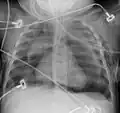

Pneumomediastinum is uncommon and occurs when air leaks into the mediastinum. The diagnosis can be confirmed via chest X-ray showing a radiolucent outline around the heart and mediastinum or via CT scanning of the thorax.